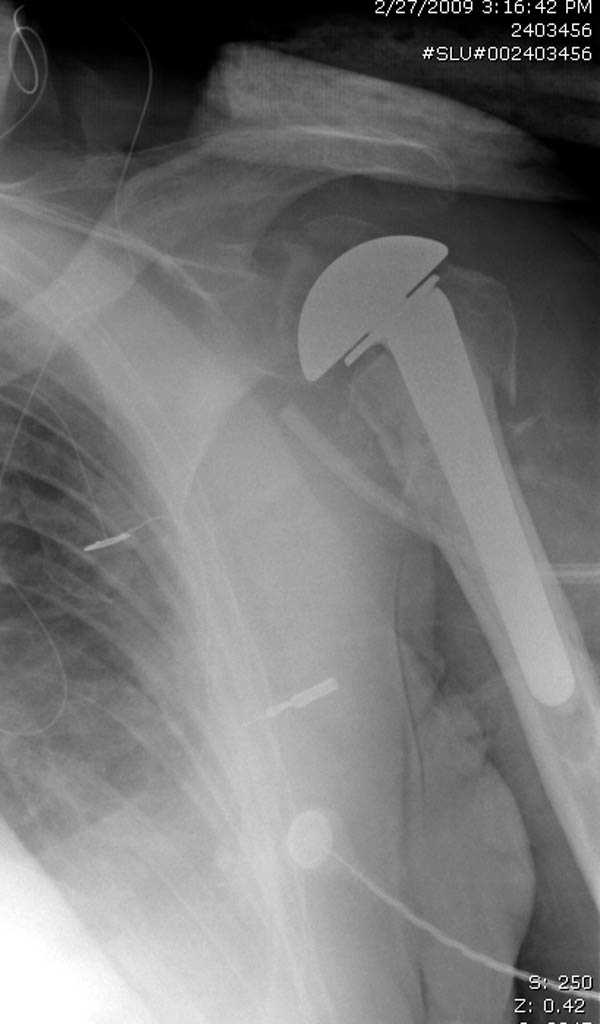

Re: Шейка плеча

дополнительные снимки по протезированию